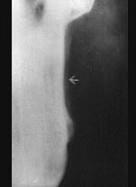

问题 边缘性骨髓炎好发于 ( )

选项 A.上颌骨体部 B.下颌升支 C.上、下颌牙槽骨 D.下颌骨体部 E.上颌结节

答案 B